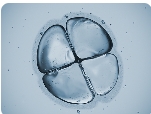

試管嬰兒技術(shù),又稱體外受精-胚胎移植(IVF-ET),是一種通過體外受精的方式,將受精卵移植到女性子宮內(nèi),達(dá)到妊娠的目的的生殖技術(shù)。試管嬰兒技術(shù)是一項(xiàng)高度復(fù)雜的醫(yī)學(xué)技術(shù),需要醫(yī)生和技術(shù)人員的高超技能和嚴(yán)格操作,因此費(fèi)用也相對(duì)較高。而試管嬰兒費(fèi)用主要是由下面幾個(gè)部分組成的。